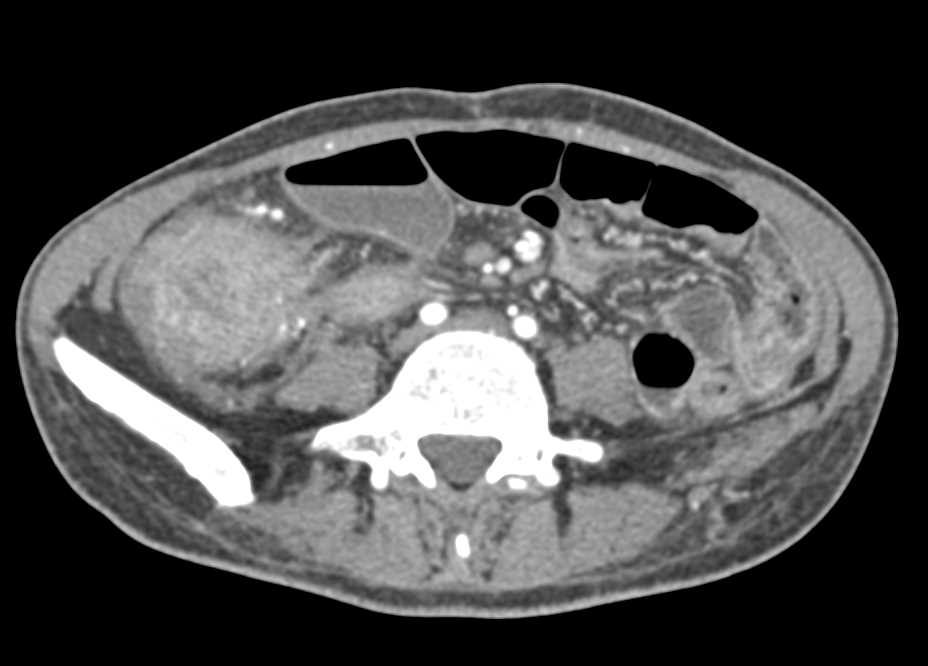

Acute Colitis Cecum with Inflammation and Some Strictures